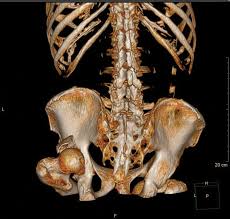

A reconstrução tridimensional (3D) é uma técnica avançada que transforma os cortes axiais obtidos durante a Tomografia Computadorizada (TC) em imagens volumétricas, permitindo uma visualização muito mais rica das estruturas anatômicas. Essa visualização pode ser manipulada em diversos ângulos, facilitando a interpretação por parte do médico radiologista e contribuindo para condutas clínicas e cirúrgicas mais seguras.

- Avaliação de fraturas complexas (coluna, face, quadril)

- Cirurgias ortopédicas e planejamento de próteses

- VR (Volume Rendering): Reconstrução volumétrica realista, ideal para face, coluna e extremidades

- SSD (Shaded Surface Display): Superfície sombreada, usada em ortopedia e crânio